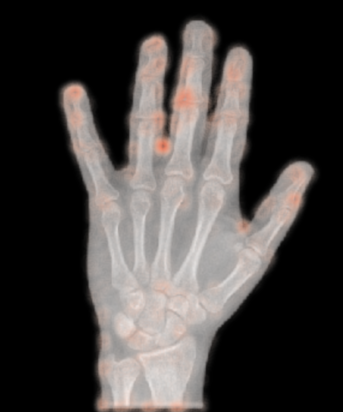

4.2 Qualitative Results

In addition to the numerical results we also showcase some qualitative results. For all methods with reconstruction loss, i.e. all AE as well as -GAN, we can generate heatmaps visualizing the pixel-wise losses. Thereby, we can highlight regions that could not be reconstructed well. Following our assumption, these regions should be the anomalous regions. In Figure 5, we can see prototypical examples produced by CAE. The upper image shows a hand contained in a study which was labeled as normal. We can see that the reconstruction error does not occur concentrated, but is rather spread widely across the hand. The maxima seem to occur around joints, which due to their more complex structure are likely to be harder to reconstruct. Compared to the lower image, which shows a study labeled as abnormal, we see a clear highlighting at the middle finger. Visible also for a non-expert, we can spot metal parts in the X-ray image at the very same location. For those anomalies which could be validated by a person without a medical background, the highlighted regions seem to correspond largely to those anomalous regions.